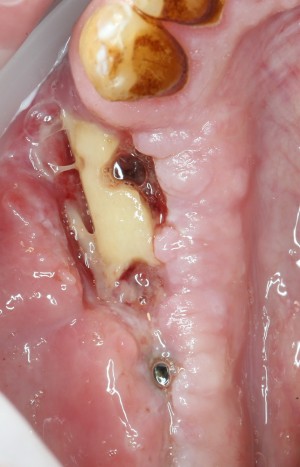

Не моя работа (мне пришлось переделывать), но причины неудачи на фото выше вполне очевидны. Недостаточное внимание к слизистой оболочке и наложению швов привело к тому, что аутокостный фрагмент инфицировался и лишился способности к интеграции. И в таких случаях бесполезно пытаться сохранить импланты (доктор уже удалил их) и сам графт — только удаление и последующая переделка остеопластики, плюс повтор имплантации. Неприятно.